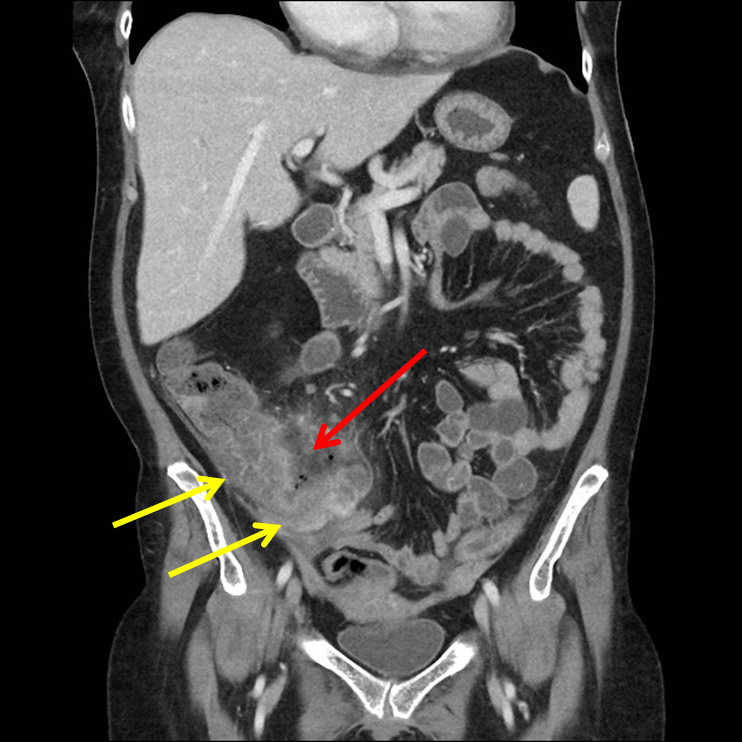

History: 50 year old female with right lower quadrant pain.

Typhlitis is a necrotizing process of the cecum, occurring in neutropenic patients who are usually receiving combined chemotherapy. The atonic cecum is affected because of its poor arterial perfusion, the presence of colonic bacteria, and the milieu of immunosuppression.

Gross and histologic examinations may reveal bowel wall thickening, discrete or confluent ulcers, mucosal loss, intramural edema, hemorrhage, and necrosis. Various bacterial and/or fungal organisms are often seen infiltrating the bowel wall.

Computed tomography (CT) is the preferred imaging modality for diagnosis. Both oral and intravenous (IV) contrast should be given, when feasible. However, oral contrast is sometimes not tolerated in patients with severe gastrointestinal tract symptoms, and IV contrast is typically avoided in patients with renal insufficiency.